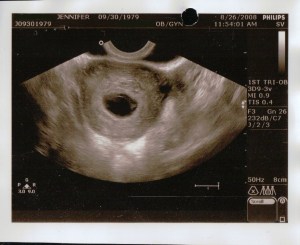

This image was during the transvaginal ultrasound, again the dark ovular hole in the center is the sac. I was supposed to be 11 weeks and 3 days along, but the sac was empty (blighted ovum 😦 ) and was measuring at only 6 weeks.

The next day by the time I was at the drs at 11:30am the bleeding had stopped entirely and my pad was completely clean. We went in for the ultrasound on Tuesday August 26 when I should have been 11 weeks 3 days along according to my LMP. I could barely move because I had to pee so bad so the tech told me she’d take a quick look and then have me empty. She did the abdominal ultrasound and said that I did a great job filling up my bladder (yippy, do I get a gold star?!), she pointed out the sac and said that we’d have to go internally to see the baby because it’s still so small.

She had me go to the bathroom to empty completely. Woohoo! I was thrilled because I was so uncomfortable. I peed as much as I could but when she started to do the transvaginal ultrasound she said that my bladder was still too full and sent me to empty again. Okay. She tried the transvaginal ultrasound again, and she again mentioned that my bladder wasn’t empty, but it must’ve been ok because she continued the exam. I found the transvaginal ultrasound painful but I kept quiet through it. She was moving and twisting the wand in all sorts of directions. She didn’t say anything through the whole exam until towards the end when she said that she was coming back out, she mentioned that she took a look at the ovaries and she pointed out the sac again.

(To read the story of how I got copies of these ultrasounds click here)

After a short while we were brought into a room with the same NP that I had for my first prenatal visit. First she asked about the bleeding which I explained to her. Then she told me “It looks like you’re having a miscarriage.” She said that the pregnancy hadn’t progressed since the last time that they saw me, that I was measuring at 6 weeks (when I should be almost 12), that the sac was misshapen and should be round (when the tech pointed out the sac we saw an oval shape), and this is called a blighted ovum when the sac grows, but the baby doesn’t. Then she said something about a “rod”, but my husband and I heard two different things. I thought I heard her say that “All we’re seeing is a rod when we should be seeing a baby by this point.” And my husband thought he heard her say that, “We’re not even seeing a rod when we should be seeing a baby by this point.”